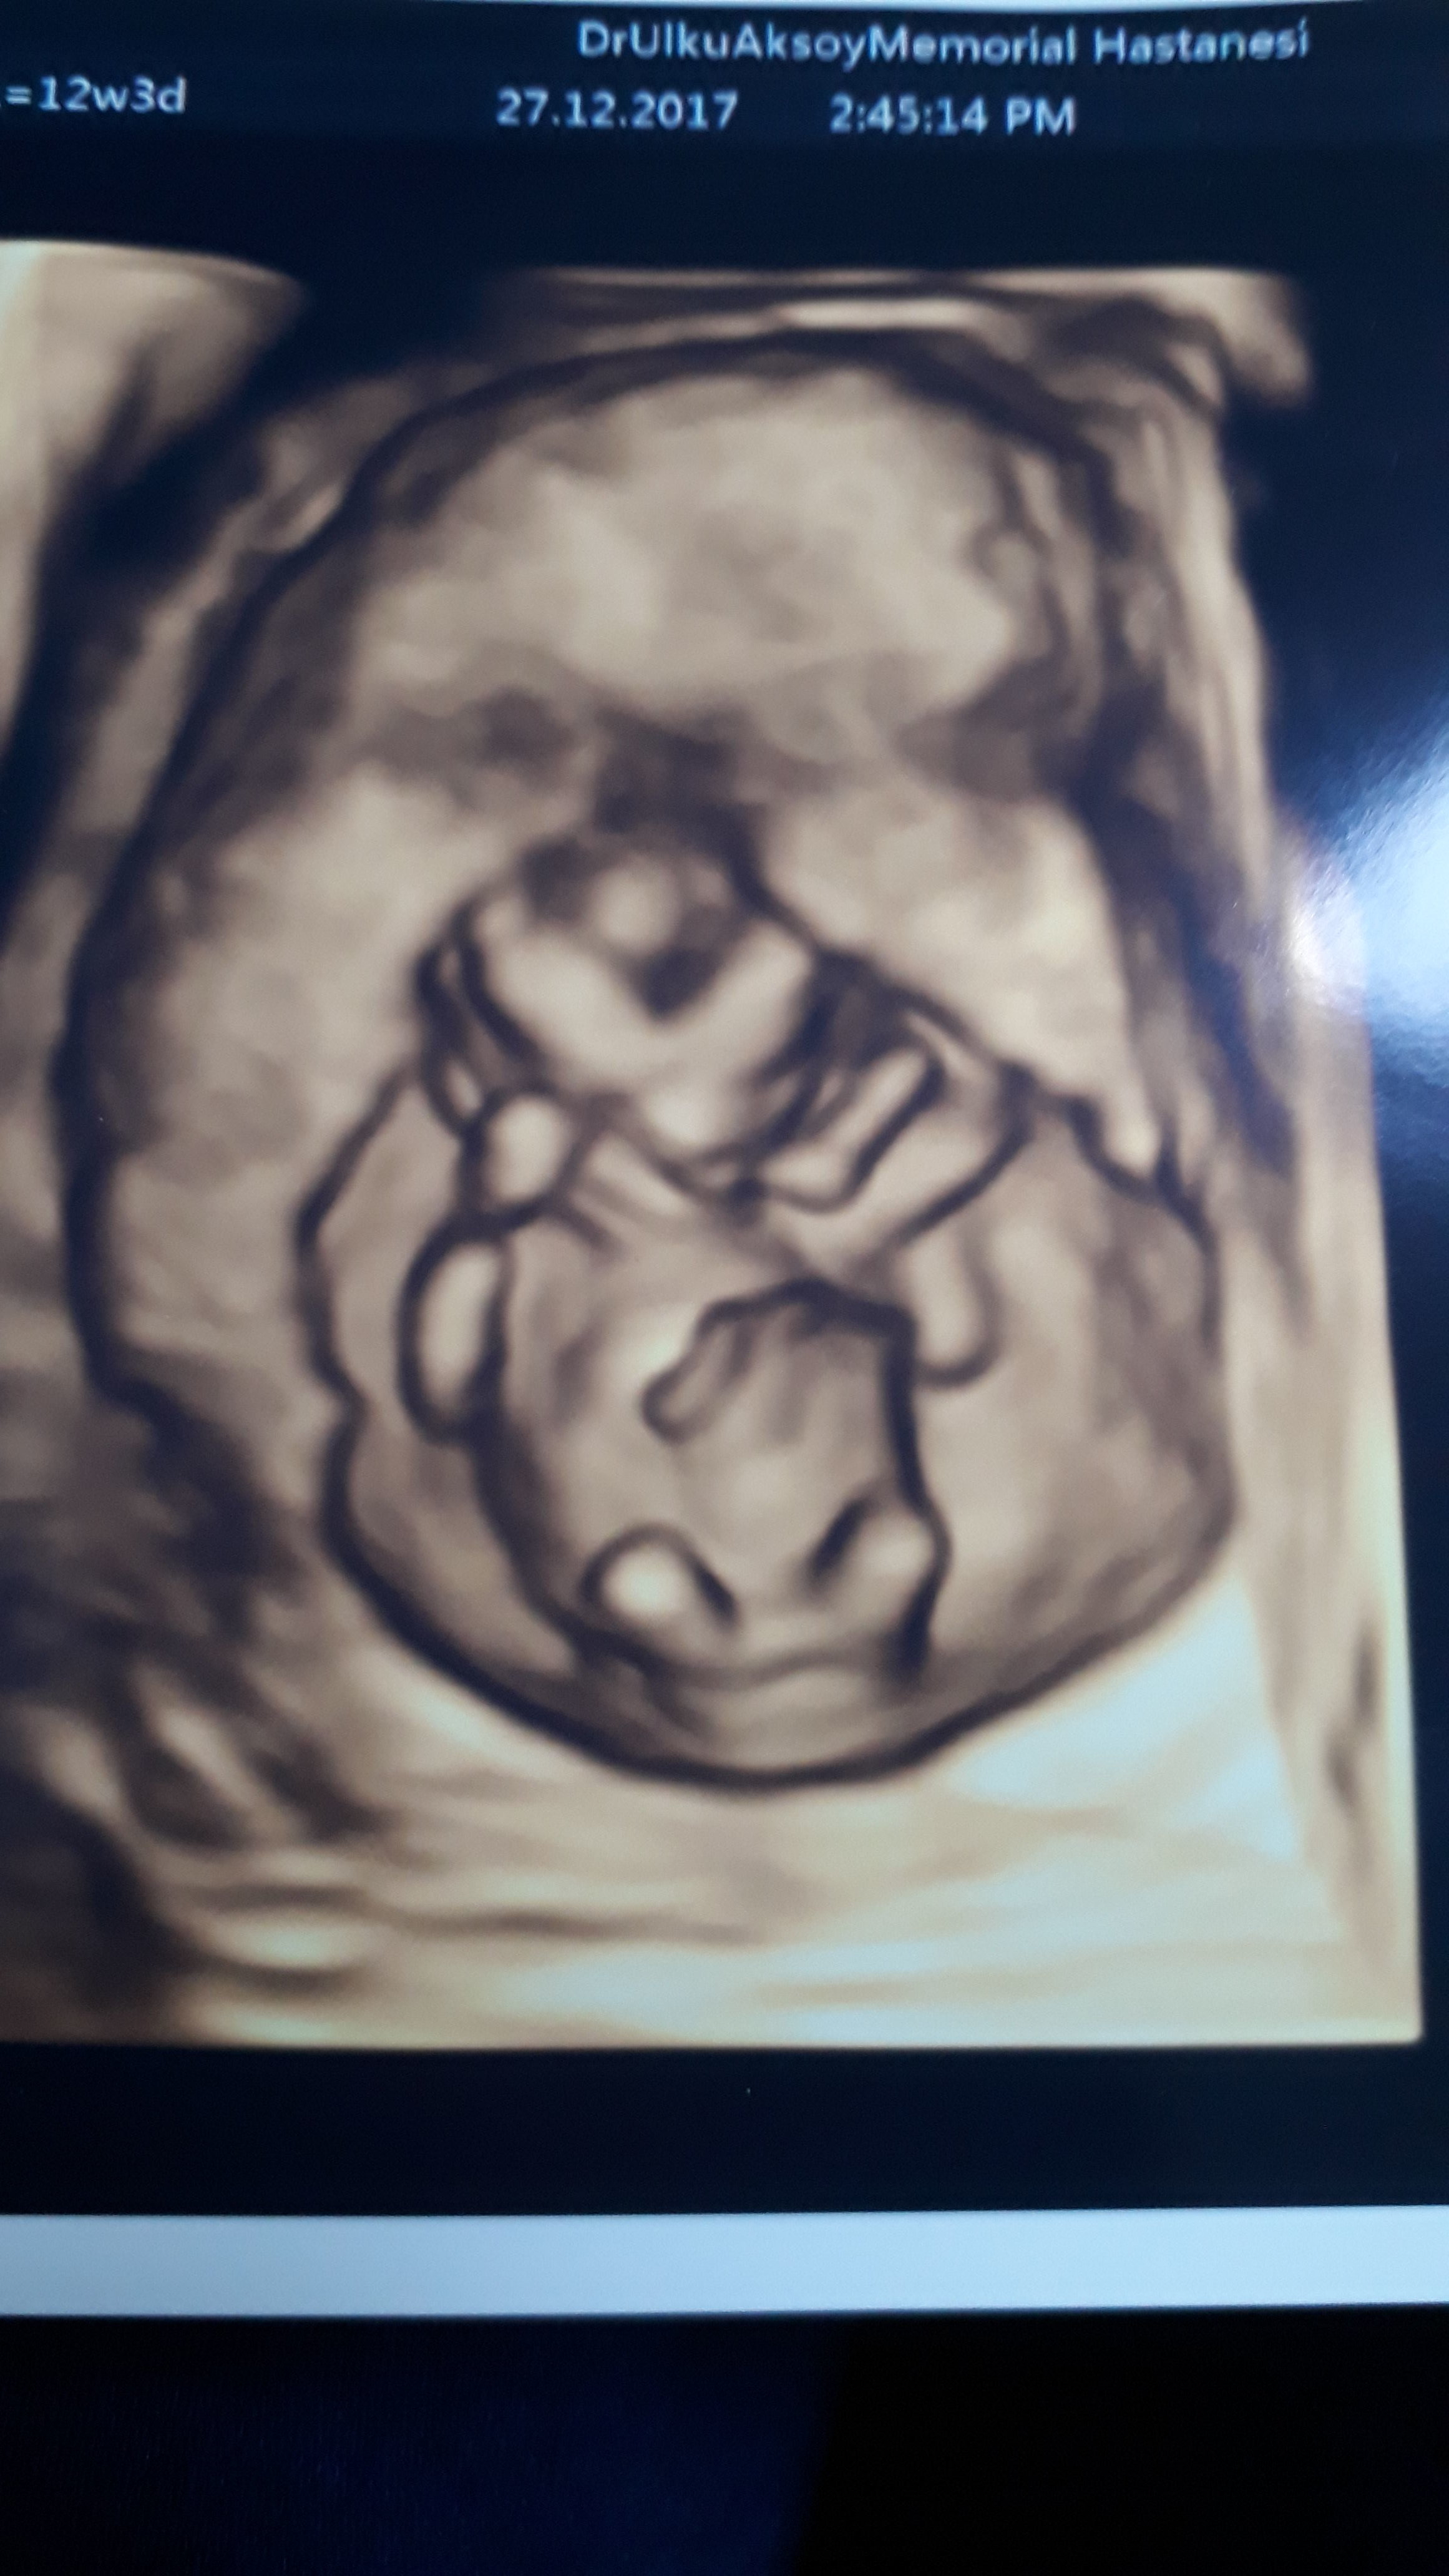

12+6 haftalık . Cinsiyetini yorumlayabilirmisinjz.dr um tam göremediği için birşey diyemedi. IMG-20171227-WA0007.jpeg IMG-20171227-WA0003.jpeg

Merhaba esila , yüklemiş olduğunuz görselde nub çıkıntısı belirgin değil. Dolaysıyla değerlendirme yapamıyoruz . Bebeğin cinsiyeti 16-17- 20 . haftalarda net olarak izlenebilir. Sağlıklı gebelik geçirmeniz dileği ile.